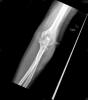

Fractura supracondílea de codo.